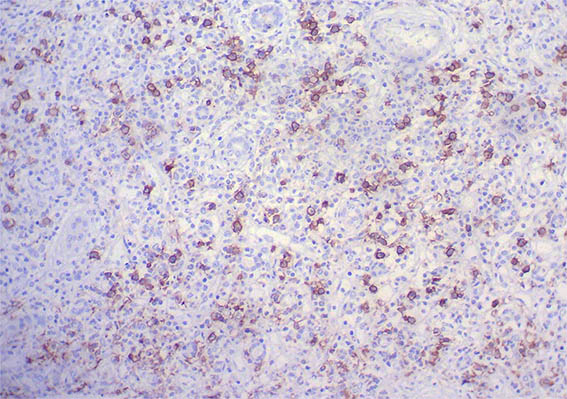

Figura 9. Inmunohistoquímica para IgG, X200. Abundantes células plasmática positivas para IgG, muchas de ellas IgG4: ver las imágenes 11 y 12.

Figura 10. Inmunohistoquímica para IgG, X400.